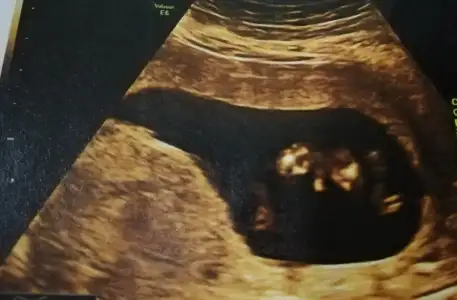

Dün gece karnımda yoğun kasılma sertleşme bebekte toplanma yaşadım. Hastaneye muayneye geldim. Doktorum izindeydi başka doktora muayne oldum. Hiç memnun kalmadım doktordan. Ama şükür herşey yolunda görünüyor. Bu arada kesin erkek netleşmiş oldu..

Geçmiş olsun çok şükür iyiymiş bebişin. Görüntüden bir şey anlayamadım. ??